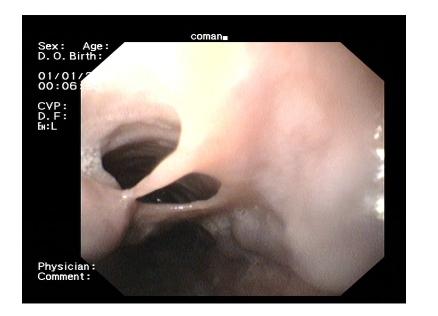

Spontaneous esophageal mucosal dissection in a patient with upper digestive bleeding and esophageal varices.

We present a case of mucosal esophageal dissection in a 44-year-old patient with alcoholic cirrhosis admitted for upper digestive bleeding. The endoscopic aspect was of chronic mucosal dissection in the esophagus and 3rd degree esophageal varices with red signs. To our knowledge, it is the only case with spontaneous esophageal mucosal dissection and portal hypertension with esophageal varices.